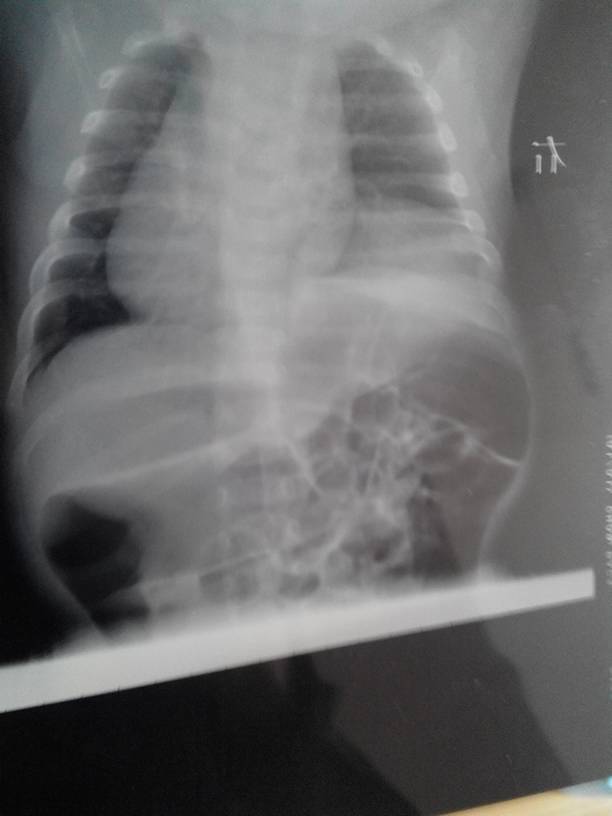

我小孩现在出生2月被检查出膈膨升,医生说小孩到了三个月后做手术,开刀,这么小就做手术,对以后发育有 我小孩现在出生2月被检查出膈膨升,医生说小孩到了三个月后做手术,开刀,这么小就做手术,对以后发育有影响吗,恢复的快吗,有后遗症吗,费用要花多少钱, 点击展开 匿名用户 2014-04-04 16:56 为您推荐: 其他回答 病情分析: 这个情况考虑是先天性的, 指导意见: 你好,目前这个问题我建议外科检查,一般是不影响的。 白其雨_6xwx 2014-04-04 17:31 相关问题 医生说说为什么小孩爱打膈 宝宝出生的时候体重偏大,顺产的时间太久了,所以导致孩子生出来窒息了,医生当时就给小孩打氧气,抢救